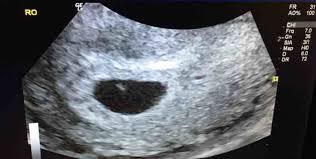

6 weeks 2 days scan no fetal pole. There are several factors involved in the detection of a healthy foetus like the size of the gestational sac menstrual cycle measurement error and so on. Hi everyone so i went for an early scan last week the tech measured me at 6 weeks 2 days due to the size of my gestational sac and we also saw a yolk sac but no fetal pole was seen im worried sick as i do not have many pragnancy symptoms the tech did not really seem worried she said i was a tad too early but everywhere i read you should. The pregnancy is not viable if however you go to the follow up ultrasound and there s still no sign of a fetal pole or a gestational sac which looks like white rim around a clear center a miscarriage has likely occurred.